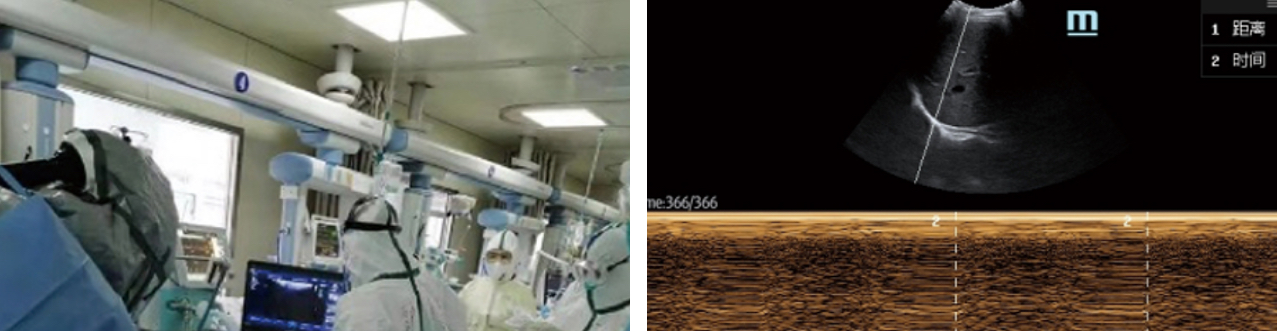

- 2. For mechanical ventilation, measure the airway diameter limit and select the appropriate ventilation tube diameter; observe the movement of the diaphragm and guide the ventilator offline